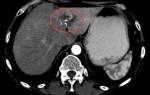

Новообразования в мозге как злокачественные, так и доброкачественные

О росте опухоли в голове человек может узнать не сразу.

По мере ее роста она начинает давить на участки мозга, что вызывает головные боли, ощущение распирания головы, тошноту, рвоту, повышение температуры и головокружения. С каждым разом состояние человека ухудшается.

Здесь нужно действовать быстро и максимально правильно. Поэтому о самолечении не должно быть и речи. Только обращение к квалифицированным и опытным специалистам!